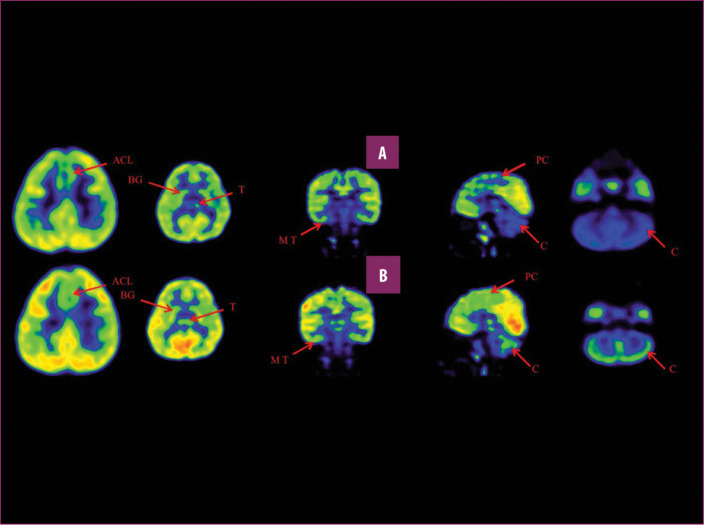

前扣帶回 (ACL)、頂葉皮層 (PC)、內側顳葉皮層 (MT)、基底神經(jīng)節 (BG)、丘腦 (T) 和小腦 (C)。B 行)第一次移植后6個(gè)月后PETCT腦部掃描的干預后圖像顯示標記區域有所改善。藍色代表代謝減退區域。綠色代表正常的新陳代謝區域。圖A和B的比較顯示藍色區域顯著(zhù)減少,綠色區域增加,這表明大腦的新陳代謝得到改善。

與之前的情況相比,他在矢狀面和額狀面上的體重變化有所改善;頭部、軀干和骨盆的排列也得到改善,雙側腿筋和小腿肌肉的緊繃感也有所減輕?;颊唛_(kāi)始執行雙手任務(wù)。在認知方面,由于他定期上學(xué),他的注意力持續時(shí)間和久坐耐力也得到了改善。GMFM評分從60.67提高到67.75;GMFCS等級由Level3提升至Level2;和FIM評分從97分提高到99分。在比較第一次細胞治療之前和之后七個(gè)月期間進(jìn)行的腦部PETCT掃描結果時(shí),前扣帶葉、頂葉皮層、內側顳葉皮層、丘腦、基底神經(jīng)節和小腦(表格1)。